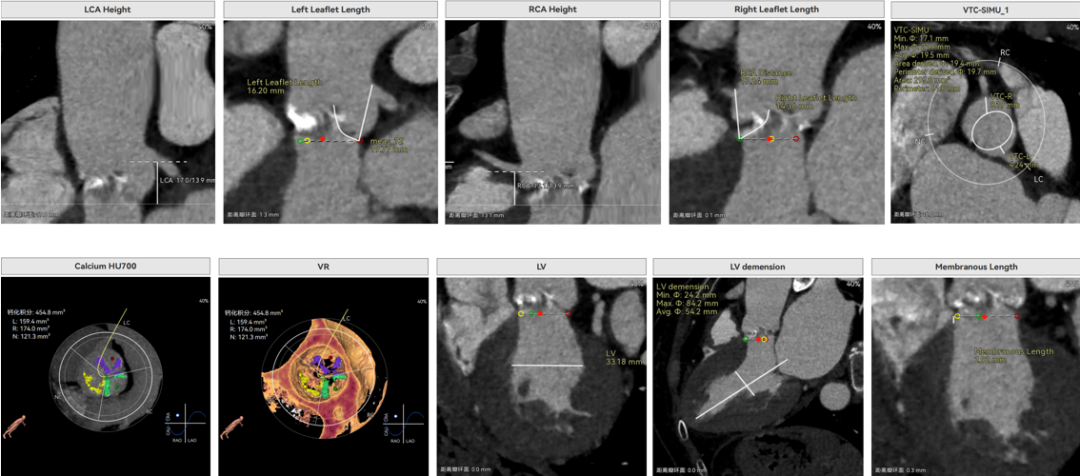

修建成教授 南方医科大学南方医院(点击查看专家详细简历) 细微之处防未然,创新携手寸寸安: 愈知临床无小事,任何风险的蛛丝马迹,都可能牵动全局。我常对团队说,真正的严谨,是将所有潜在 scenario 视作必然,在术前便一一拆解、化解 —— 如同在堤坝溃决前便筑牢每一寸基石,让风险连萌芽的机会都没有。 此次应用全球首创的预装干瓣,是基于对患者的综合考量,拥抱创新,实践创新,让创新携手助力“万全之策”的重要环节。 术前推演需要结合器械的特性:深度了解才能得心应手,结合患者基础病的相互影响并落实到术后 72 小时的并发症预警,每个环节都要像精密齿轮般咬合无误。这份 “穷尽万一” 的准备,从来不是对完美的苛求,看似耗时费力,实则是对生命最质朴的承诺 ——以医者的周全,携手创新的产品,为患者的万无一失不断努力! 患者病史 因 "反复胸闷伴活动后呼吸困难 3 年" 入院:患者 3 年前无明显诱因反复出现胸闷,部位在前胸,有憋气感,间有心悸,伴有活动后呼吸困难;外院就诊,查心脏彩超示 "主动脉狭窄、二尖瓣关闭不全"; 既往有高血压 20 余年,长期服用氨氯地平阿托伐他汀钙片降压治疗;有糖尿病 1 年,长期服用二甲双胍、阿卡波糖降糖治疗。 术前超声提示:主动脉瓣增厚、钙化并狭窄(重度)及关闭不全(轻度) 术前超声提示:主动脉瓣增厚、钙化并狭窄(重度)及关闭不全(轻度) 术前CT Type1型(R-N)二叶瓣,中度钙化集中在左窦瓣叶边缘及右无交界处,主动脉根部直径21.6mm,LVOT直径22.2mm,瓣上限制逐渐增大;双侧冠脉开口高度可,瓣叶短,窦部宽度足够,双冠VTC空间>4mm,预估冠脉风险小。 左室腔小,室间隔膜部短,有一定PPI风险;外周双侧入路无明显迂曲,双侧髂外动脉存在散在钙化、股动脉直径大,右股低分叉,能够支持20F大鞘通过。 手术策略 推荐右侧股动脉为主入路,放置20F大鞘,左侧为辅助入路,常规穿刺;使用20球囊预扩,预装AV23瓣膜;左右重叠位:RAO 1° CAU 28° ;右窦居中位:LAO 22° CAU 0° ;左冠切线回调:LAO 35° CRA 17° ;心室小,术前术中积极补液调整容量,做好循环崩溃处理准备。 手术过程 主动脉根部造影 20mm球囊预扩 - 无腰无漏 瓣膜初始定位 工作位观察瓣膜 - 冠脉通畅,位置合适 最终造影观察 - 无瓣周漏、挂钩处于最右方-Commisural Alignment 术前压差120mmHg,术后压差2mmHg。 Prostyle A®预装干瓣——助力临床最优化解决方案: 平衡的径向支撑力:该病例为TYPE 1型二叶瓣,对产品的径向支撑力是一种考验,术后影像彰显Prostyle A®综合设计带来平衡的径向支撑力,轻松应对高钙化病变,符合中国国情,为二叶瓣患者带来信心保障; 轻松过弓,精准可控:该病例主动脉弓角度可,但弓距小,考验产品的通过性能,术中顺利过弓,未使用snare轻松过弓; 预装干瓣 便捷顺安:金仕生物专利抗钙化技术运用纳米技术去除组织内的细胞碎片和磷脂,封闭游离醛基,从根本上阻断了瓣膜钙化的多项因素,显著提升了瓣膜的耐久性;同时,相比较传统戊二醛保存方式,干式存储最大限度的保留心包的亲水亲油平衡,还原组织天然曲柔性,进一步保障了瓣叶开合,保证长期耐久性。